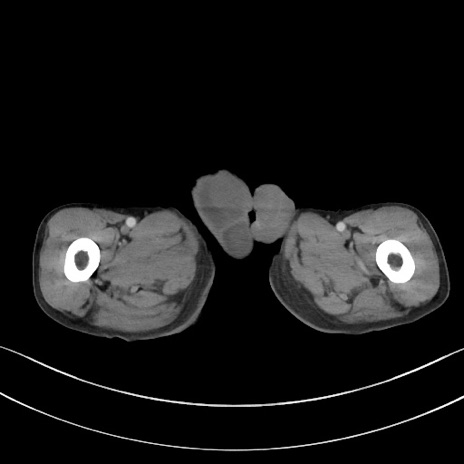

冠状断像

矢状断像

【症例】 70歳代男性

【主訴】右鼠径部腫瘤、疼痛

【既往歴】膀胱癌にて膀胱全摘、両側尿管皮膚瘻